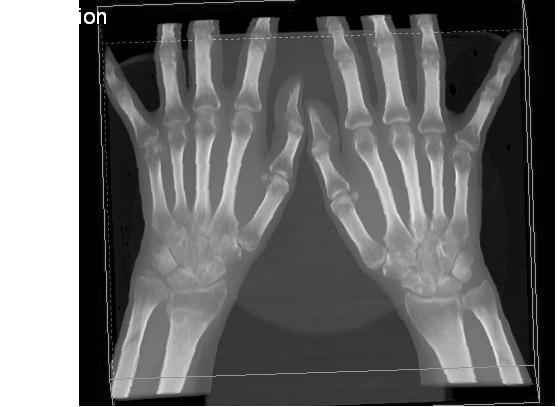

Уважаемые коллеги.Прошу обсудить случай лечения перелома дистального метаэпифиза лучевой кости. Ситуация скандальная и крайне неблагоприятная. Больная с патологической обстоятельностью мышления, склонностью к сутяжничеству, патологическими умозаключениями, не поддающимися коррекции (см. психиатрию, правда офиц. диагноза нет). В данном случае есть ряд ошибок с нашей стороны, прежде всего в отношении качества ведения документации (за что получил административное взыскание, по делом мне дураку). В остальном- придерживались в лечении подхода классический советской школы. Так как умную операцию…… сами знаете… 15.12- перелом луча в Москве. Там же репозиция, гипс. Дальнейшее лечение у нас в ЦРБ. 20.12.- вторичное смещение в гипсе21.12- под внутривенным наркозом- репозиция, гипсовая лонгета. Дальше начинается самое интересное. После репозиции больная заявила, что я (репозицию делал я) порвал ей все связки в суставе, посинел у нее 5 палец, якобы я за него тянул и т. д. На самом деле на 2 сутки после репозиции рука немного отекла и было незначительное сдавление гипсом, который был ослаблен. Дальнейшее лечение консервативное. Через 6 недель- гипс снят, назначено ЛФК. Пациентка крайне недовольна. Говорит, что на снимке у нее выступает кость, я ей сломал руку и.т.д. В общем началось. Пациентка прочитала в интернете наверное все, что есть по данной травме.По заключениями рентгенологов и консультанта из КДЦ областной больницы - стояние отломков допустимое. Объективно говоря- снижена высота лучевой кости, диастаз лучелоктевого сочленения, и не сросся шиловидный отросток. однако на РКТ при сравнении с другой стороной- разница незначительная. Дальше в одной из больниц нашей области и одной из больниц Москвы (вроде бы КГБ 53) врачи сказали, что репозиция сделана плохо. Нужна операция (восстановить длину лучевой кости), даже один из них предложил РЕДРЕССАЦИЮ (хи-хи) с наложением аппарата Илизарова. Что это для данной больной- радость неописанная. (см. описание психического статуса). Ничем другим, кроме зарабатывания дешевого авторитета объяснить данный факт не могу.Кстати, у больной еще нейропатия локтевого нерва.Для разрешения конфликта больная направлена на консультацию в ЦИТО на 03.03.11.

Теперь вопросы: 1.Прошу объективно оценить качество нашей репозиции на момент 21.12. (неужели так плохо?). Что на снимках при снятии гипса- сам вижу. 2. сравнить снимки РКТ (с двух сторон)- так ли велико укорочение лучевой кости и лучелоктевой диастаз. 3. Ваши мнения, в отношении целесообразности оперативного лечения учитывая ВСЕ вышеизложенное. 4. На всякий случай для суда- мог ли я тракцией в 2- 3 кг за 1 и 2 пальцы под внутривенным наркозом неправильно вколотить отломки и травмировать локтевой нерв. Кстати, в США если врач пациенту говорит, что его плохо лечили- то этого врача лишают лицензии. У нас наооборот- обгадить другого милое дело. И это процветает. От себя же могу сказать, что никто в нашем отделении так не поступает. Коллеги, будьте осторожны в своих высказываниях. От осложнений и ошибок никто не застрахован. А в данном случае многое будет зависеть от заключения консультантов поликлиники ЦИТО, куда больная направлена областным травматологом на 03.03 для решения вопроса о дальнейшей тактики лечения. С уважением ко всему травматологическому сообществу Дедок Михаил.

1. РЕПОЗИЦИЯ сделана качественно(ОСНОВНЫЕ 2 УГЛА ВЫСТАВЛЕНЫ ПРАВИЛЬНО ) , но перелом нестабильный и склонен к втор смещению . Поэтому мы стараемся все переломы со смещением фиксировать 3-МЯ спицами по GRIN методике .

2. По сравнению и без ! втор смещение незначительное.НЕТ НИКАКОЙ ,,локтевой косорукости,,маделунгов . но имеется смещение совести у врачей КГБ 35--НЕТ ЗДОРОВЫХ, есть только недообследованные ! Этому смещению аппарат внешней фиксации не поможет .Психопаткам в менопаузе да весной только этого и надо чуть толкнули и поехало .

1. Репозиция от 21.12.10 была выполнена лучше, чем первичная.

2. Укорочение лучевой кости с изменениями дистального лучелоктевого сустава требует оперативного лечения